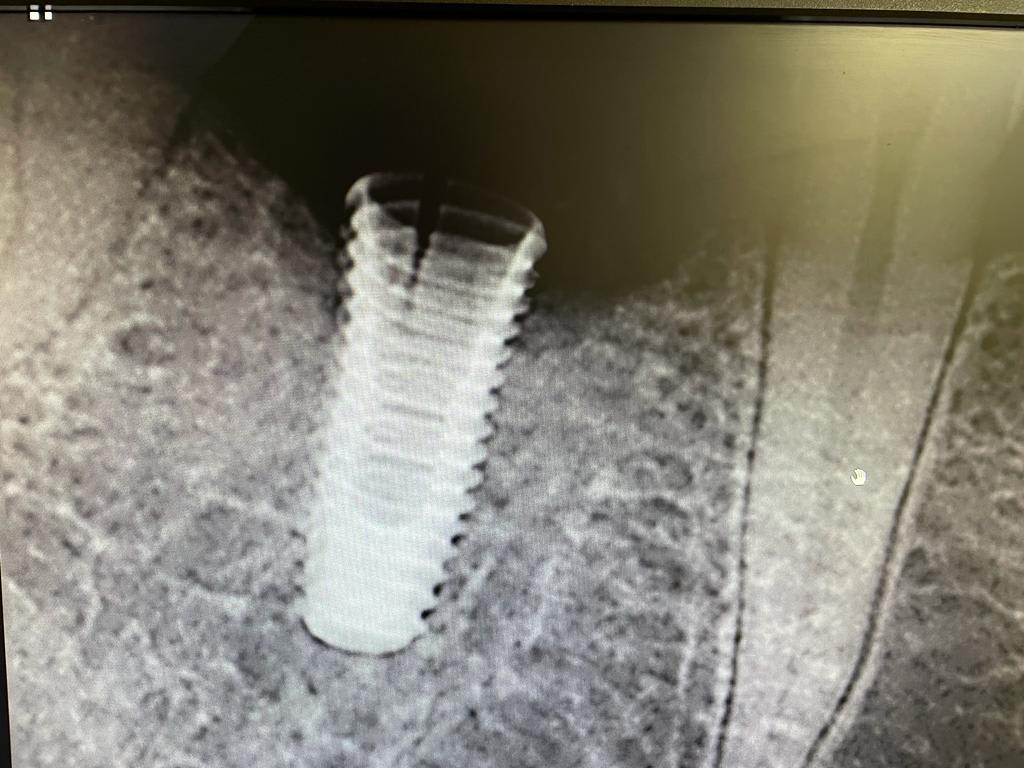

Implant dentium Superline 4x10 posé en 46 debut 2018 sur patiente bruxomane avec gouttiere.

le col de l'implant est tellement fin qu'il est radiotransparent sur le radio de fatboy...

On dirait que tu es directement sur les spires de l’implant.

il semble que l os ne soit plus présent autour de l implant sur le col , y a t il un lien de cause a effet?